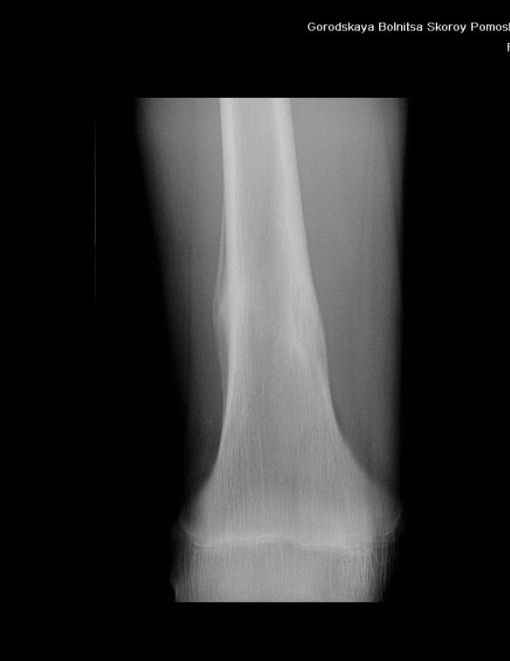

Здравствуйте, уважаемые коллеги!Представляю вашему вниманию интересный случай и пока что непонятный для меня в диагностическом плане. На днях в наше отделение (детской ортопедии и травматологии) поступил 13-летний мальчик по направлению из поликлиники с диагнозом: остеома нижней трети правого бедра.

Анамнез практически никакой: в следствие травмы (растяжение связок коленного сустава) от 07.11.2004 выполнены Rg-граммы в травмпункте и обнаружено опухолевидное образование. Первичные Rg-граммы я не публикую, так как они заметно худшего качества, да и динамики за прошедшие три недели не отражают. Болевой синдром купирован в течение трёх дней. В настоящий момент мальчика ничего не беспокоит. Ходьба не нарушена, опухоль пальпируется с трудом по задней поверхности в н\3 правого бедра, пальпация безболезненна, объем движений в суставах правой нижней конечности полный и симметричный. Кожа над опухолью не изменена.В нашей клинике проведено дополнительное обследование: общие анализы крови и мочи, биохимия крови без особенностей. Выполнены Rg-граммы на цифровом Siemens обычные и продольные томограммы срезами 3-5 мм, а также компьютерная томография поперечными срезами по 5 мм. Прошу обратить внимание, что на приведённых томограммах видны две полости 10х15 мм и 15х60 мм. Также имеются два опухолевидных образований наслаивающихся друг на друга: уплощённое и вытянутое 10х100 мм и элипсовидной формы 15х30 мм. Это хорошо заметно на фото a_1.jpg c_1.jpg и d_1.jpg. Плотность внутри полостей 125% от плотности костномозгового канала, плотность наружного опухолевидного образования 55% от плотности кортикального слоя. Также отмечается линия перелома по центру наружного опухолевидного образования.Исходя из полученных данных мнения в плане диагноза несколько разделились от 1)сочетания кортикальной фиброзной дисплазии и латентно протекавшего маршевого перелома н\3 правого бедра до 2)остеосаркомы. В отношении первого варианта не сходится отсутствие клиники при переломе такой крупной кости как бедро, второй вариант вообще оставлю без комментария, ибо некомпетентен. Хотелось бы услышать мнения коллег, с удовольствием ознакомлюсь с любыми предположениями и замечаниями.С уважением, Александр Е. КлоковОтделение детской ортопедии и травматологииБСМП г. Мурманска.